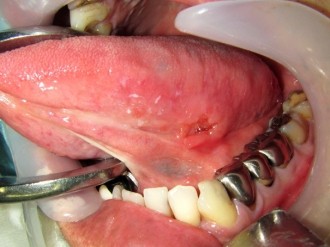

癌の発生する部位や病期(癌の進行度)によって様々です。癌表面の特徴としては、ぶつぶつしていたり、赤や白色に変色している、かたい腫瘤(こぶのような盛り上がり)や潰瘍(えぐれたような形態)を形成していることがあり、時に簡単に出血したり痛みが出ることもあります。病気が進むにつれて噛みにくさや飲み込みにくさ、発音のしにくさが出てきたり、頸部(くび)のリンパ節への転移、遠隔転移(肺、骨、肝臓等)を生じるようになります。

頬粘膜癌

上顎歯肉癌

下顎歯肉癌